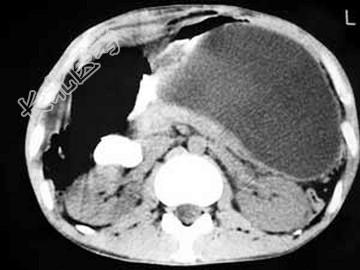

- 单项选择题男,33岁, 腹部外伤后2月余,腹部疼痛, 行CT扫描所见如图,最可能的诊断是 ( )

C、胰腺创伤性假性囊肿